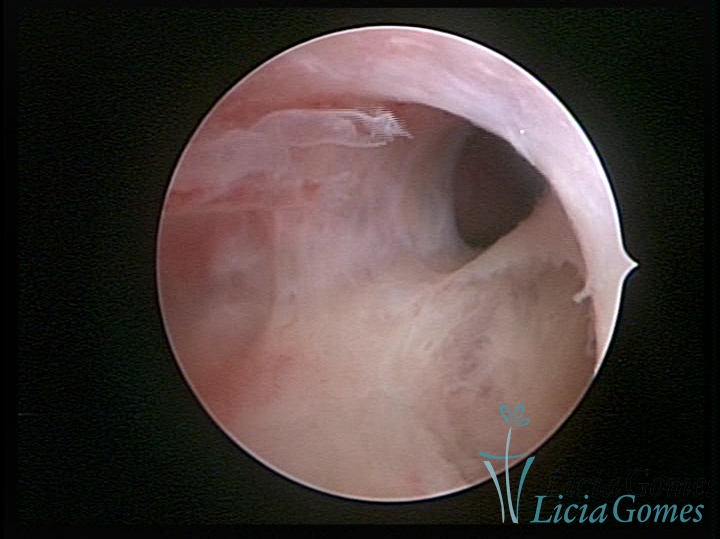

SINÉQUIA TIPO MUCOSA